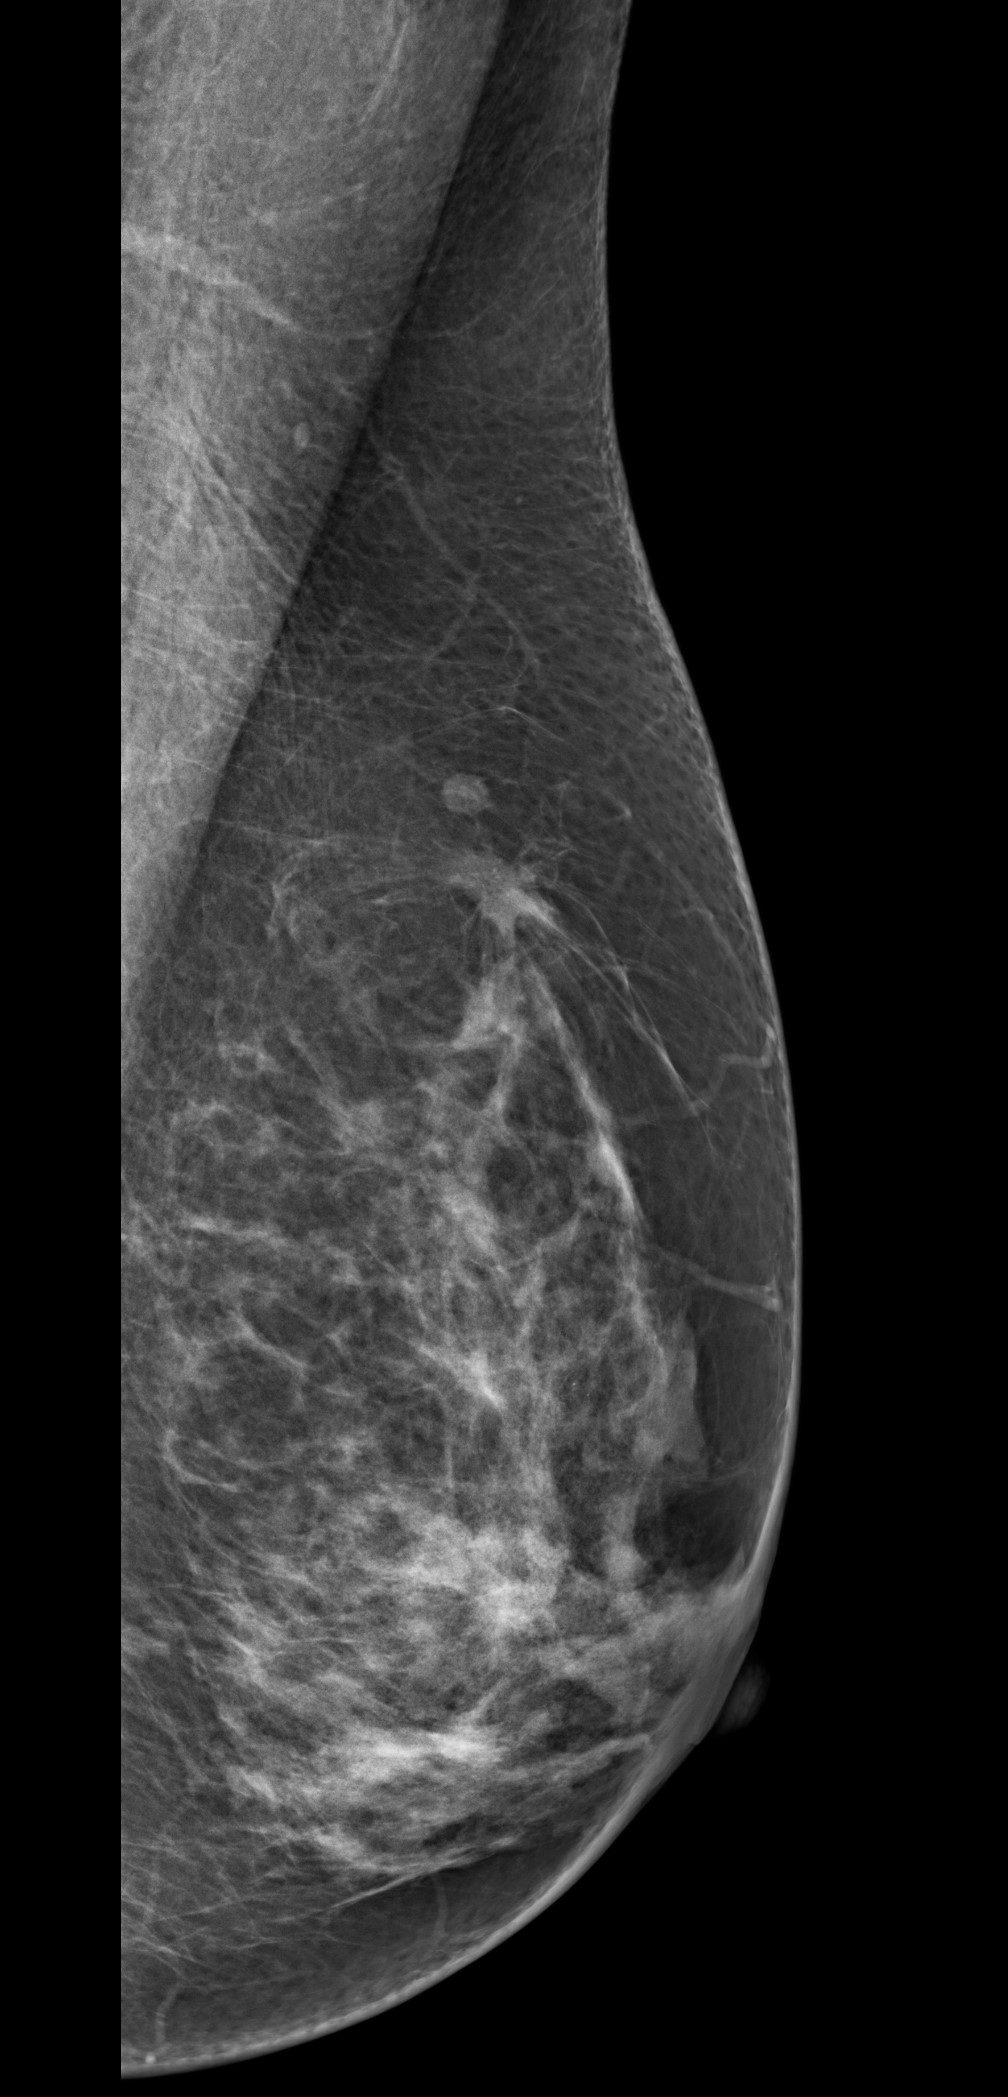

Caso 14

Luisa Maria Bermudez Rosell